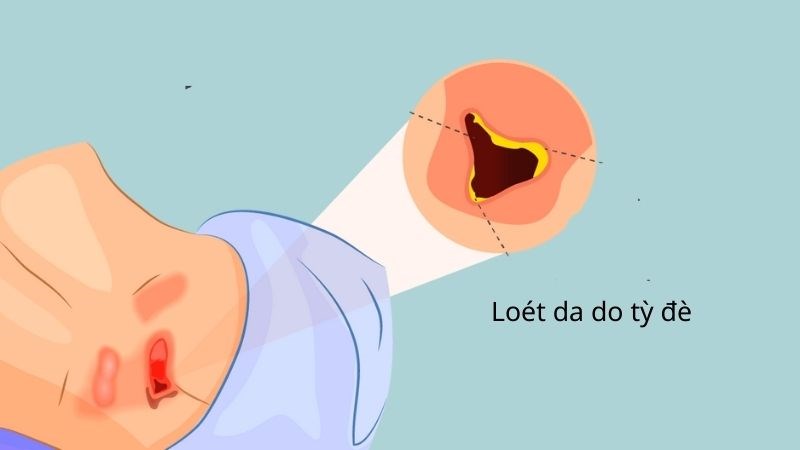

Khoa Hồi sức tích cực, Bệnh viện Hữu nghị đa khoa Nghệ An Loét do tì đè gặp chủ yếu ở người nằm lâu bởi tai biến, tai nạn, sau các phẫu thuật lớn (nhất là phẫu thuật gãy xương đùi), ít hoặc lười vận động, đặc biệt là người cao tuổi. Bệnh gây nhiều […]